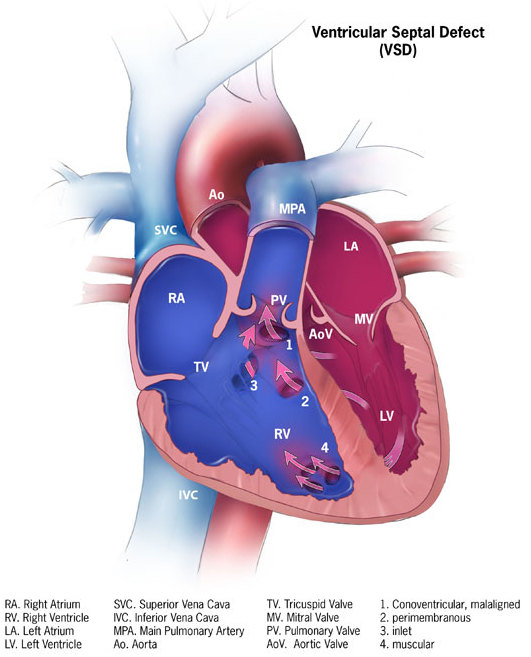

Ventricular Septal Defect (VSD)

A ventricular septal defect is a flaw in the wall that separates the right and left ventricles, or septum.

Ventricular septal defect is the most common congenital cardiac condition.

Ventricular septal defect is inextricably linked to fetal alcohol syndrome.

Ventricular septal defect results in a shunt from left to right.

Age at presentation and defect size both depend on the ventricular septal defect size.

Large ventricular septal defect can cause Eisenmenger syndrome.

Treatment of large ventricular septal defect involves surgery.

Small ventricular septal defects are frequently asymptomatic.

Small flaws might naturally close.